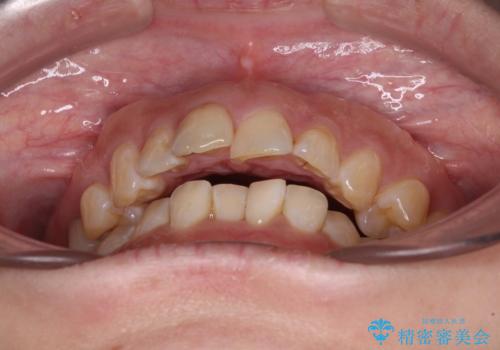

- 飛び出た上の前歯を気にして来院された患者様です。

奥歯の咬み合わせは、上顎歯列が理想的な一よりも数mm前方にある状態でした。

舌の突出癖が原因で上下の歯に大きなスペースが生じていたため、舌のトレーニングをしっかり行っていただくことで、上顎歯列をスムーズに移動させることができました。